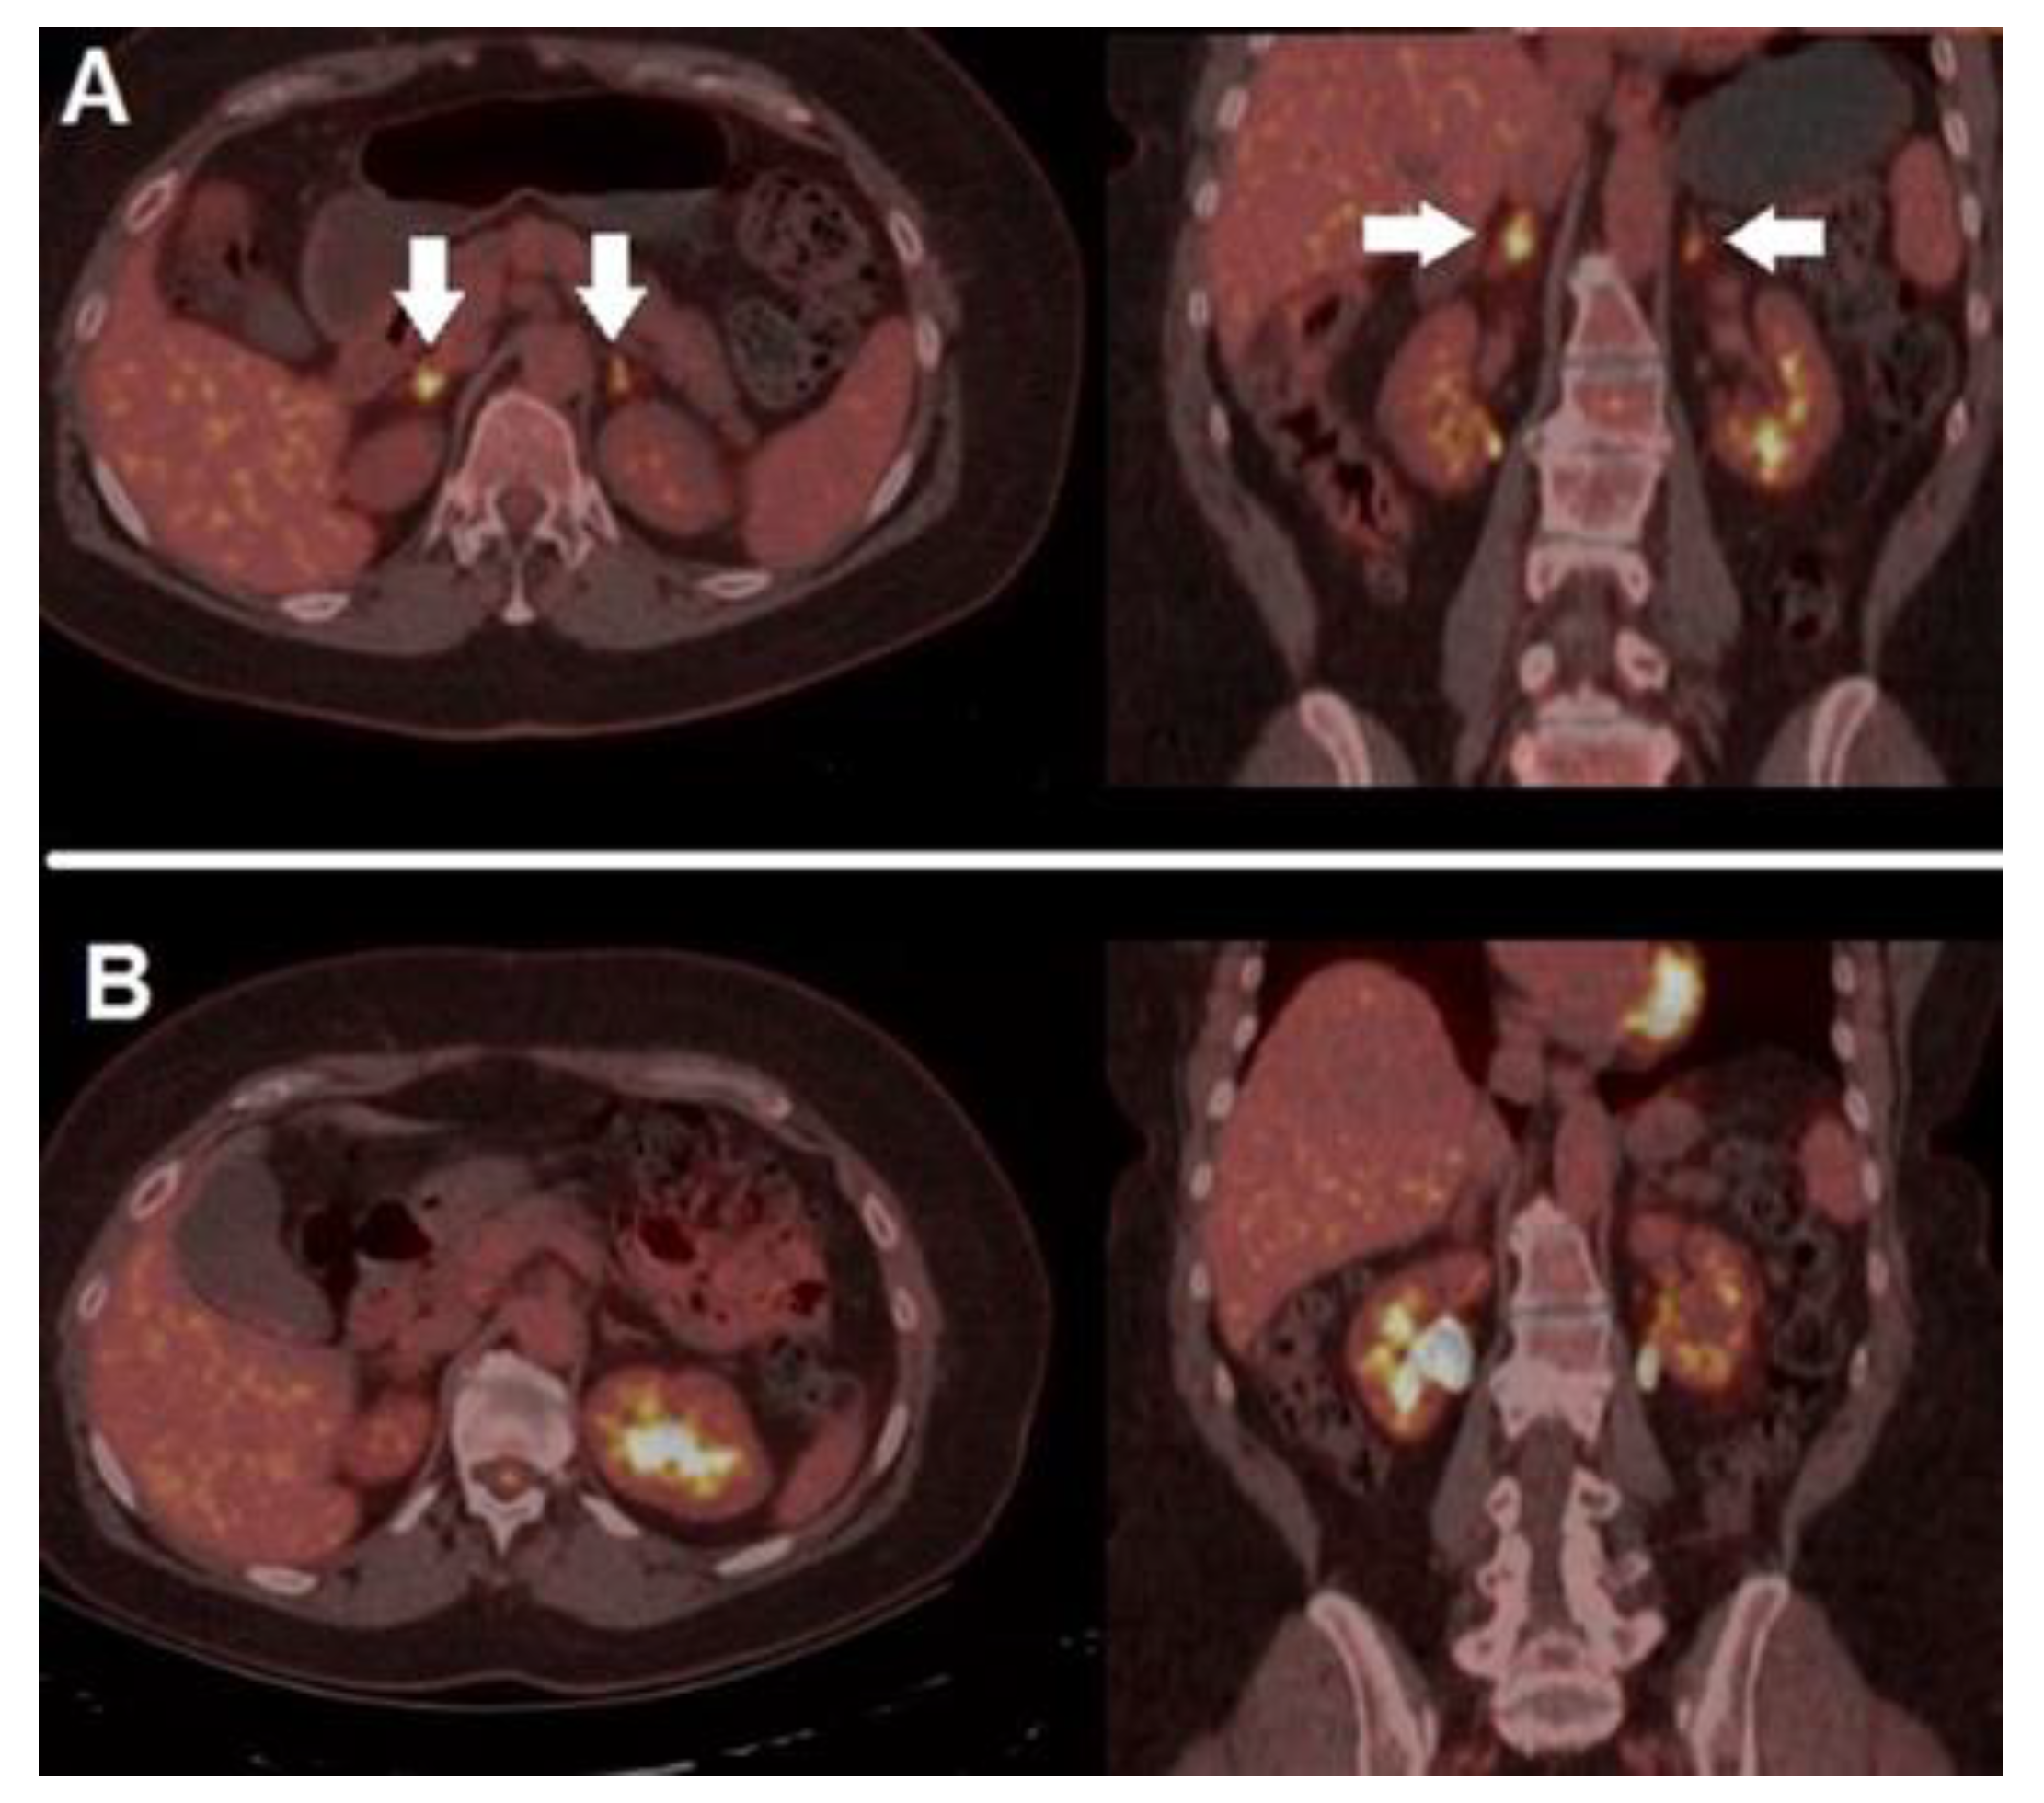

3.2. Immunotherapy: The Need for Novel Criteria

- Annovazzi, A.; Vari, S.; Giannarelli, D.; Pasqualoni, R.; Sciuto, R.; Carpano, S.; Cognetti, F.; Ferraresi, V. Comparison of 18F-FDG PET/CT Criteria for the Prediction of Therapy Response and Clinical Outcome in Patients With Metastatic Melanoma Treated With Ipilimumab and PD-1 Inhibitors. Clin. Nucl. Med. 2020, 45, 187–194. [Google Scholar] [CrossRef] [PubMed]